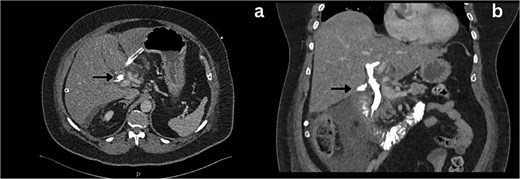

She was admitted, resuscitated, and started on intravenous antibiotics. Considering her previous history of cholecystectomy and deranged Liver Function Tests (LFTs), a clinical diagnosis of cholangitis was made. Magnetic retrograde cholangio-pancreatography (MRCP) was done, which showed significant dilatation of the biliary system extending down to the ampulla with the common hepatic duct (CHD) diameter of 23 mm with a normal pancreatic duct. Additionally, there was florid upper abdominal edema and fluid tracking along the right paracolic gutter (Fig. 1). There was no evidence of any common bile duct (CBD) stone or lesion to explain this dilatation. To further explore the underlying cause, a computed tomography (CT) pancreas was performed, which revealed no signs of pancreatitis nor any distal CBD or pancreatic lesions. The presence of fluid in the subhepatic and right paracolic regions likely indicated a bile leak (Fig. 2), but fluid related to pancreatitis could not be excluded. The findings were deliberated upon with the specialist hepatopancreaticobiliary (HPB) team and Specialist gastrointestinal (GI) radiologists. Despite extensive discussion and review with the radiologist, the nature of the fluid was not identified through the two imaging modalities employed. There was no obvious pancreatitis. A decision was reached to continue conservative management and opt for operative intervention in the event of clinical deterioration.

Coronal section MRCP imaging; a) Gross biliary dilatation (arrow), b) smooth tapering of the bile duct with no evidence of stones (arrow).